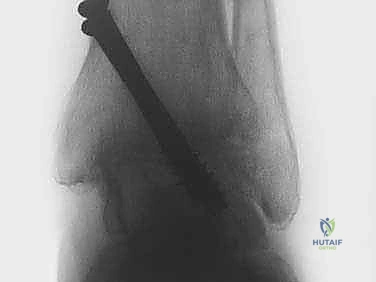

بمجرد تحضير العظام، يتم وضع القدم في الوضعية الوظيفية المثالية للمشي (عادة بزاوية 90 درجة مع الساق). يتم إدخال براغي معدنية قوية (عادة من التيتانيوم) عبر الجلد وبمساعدة الأشعة السينية الفلورية (C-arm) لضغط العظمتين معاً وتثبيتهما بقوة. هذا الضغط المحكم يمنع أي حركة ويسمح للعظام بالالتحام.